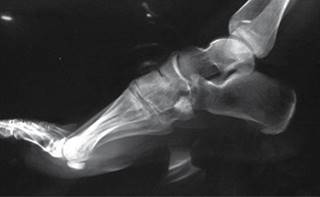

En las radiografías dorsoplantar y lateral de pie derecho se observa injerto óseo en el centro de una lesión en cuboides, radiotransparente, heterogénea, multilobulada, con bordes irregulares que sobrepasan la cortical lateral, multilobulados (Figuras 2 y 3).

Figura 3: Radiografía lateral de pie.